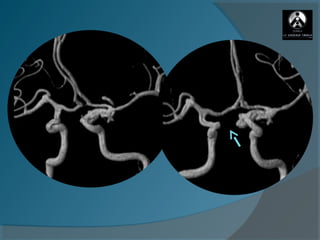

Estenosis en el sifón carotídeo (Amaurosis Fugax)

Mujer de 51 años

Antecedente AIT antiagregado

Stroke isquémico